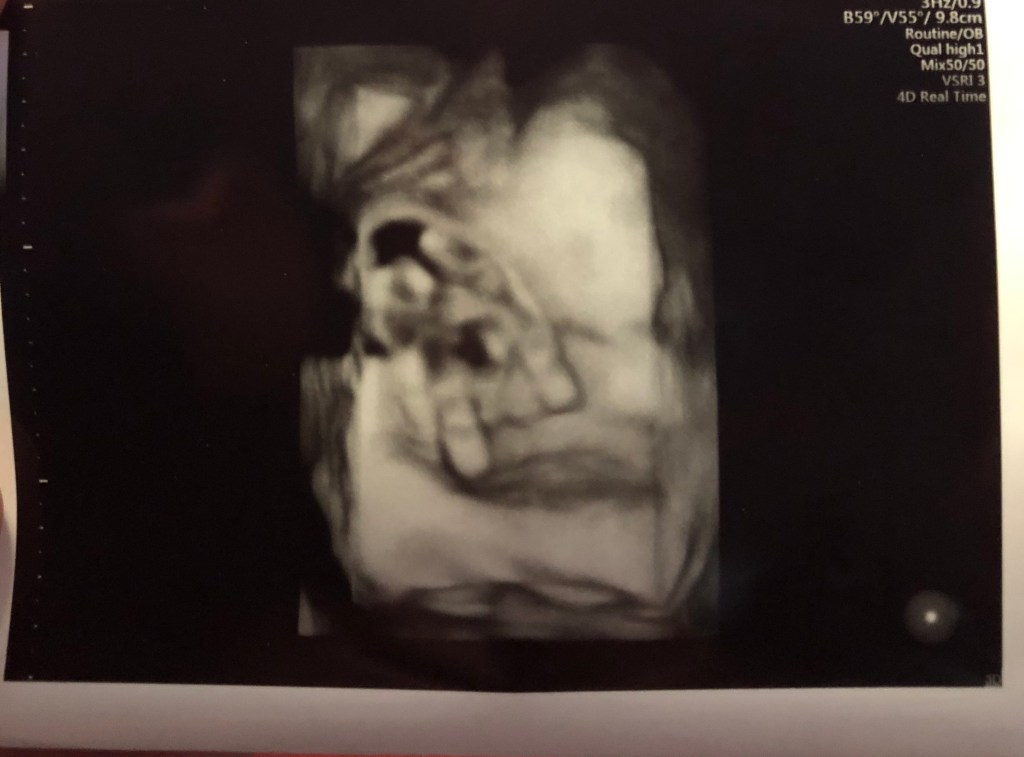

Speaking of Joshua, he seems to be growing well and staying right on track. He is just as active as Benaiah was, gives me just as much heartburn and has the hiccups just as frequently. We had a measurement ultrasound for him today and he is already 6lb 1oz! On a side note of prayer, they noticed the fluid around Joshua was a little low so I’m going back in a week to be rechecked and hopefully if I do better with my water intake, everything will be looking great. If it is still low, it could be a sign that my placenta is getting tired and we may have to make some decisions. I am choosing to focus on the positive and drinking water as I type this now!